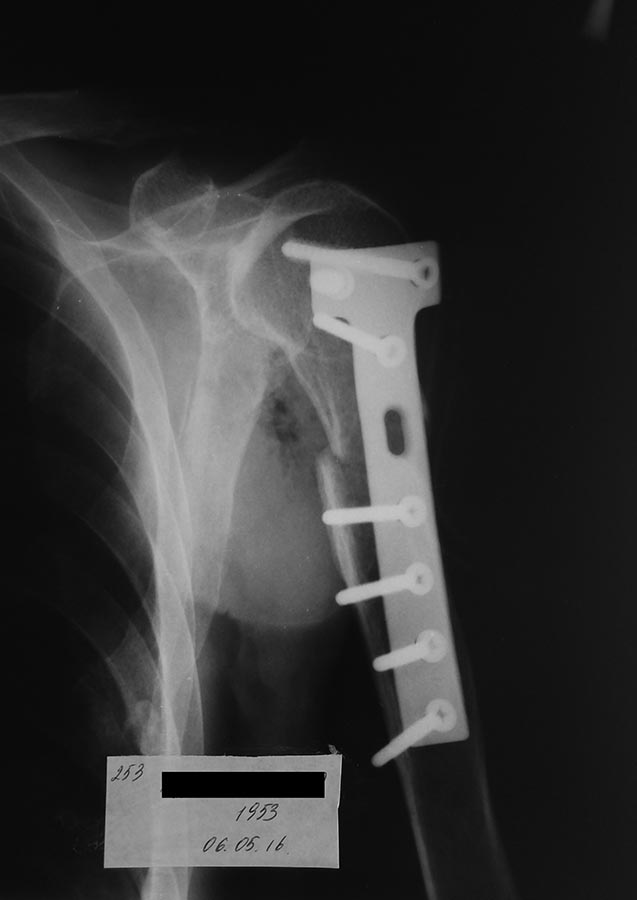

Операуия получилось удачно. При ревизии обнаружклось повреждение

дельтовидной мышчы с дистальным отломком плечевой кости.

Пришлось фиксировать Т образной пластиной